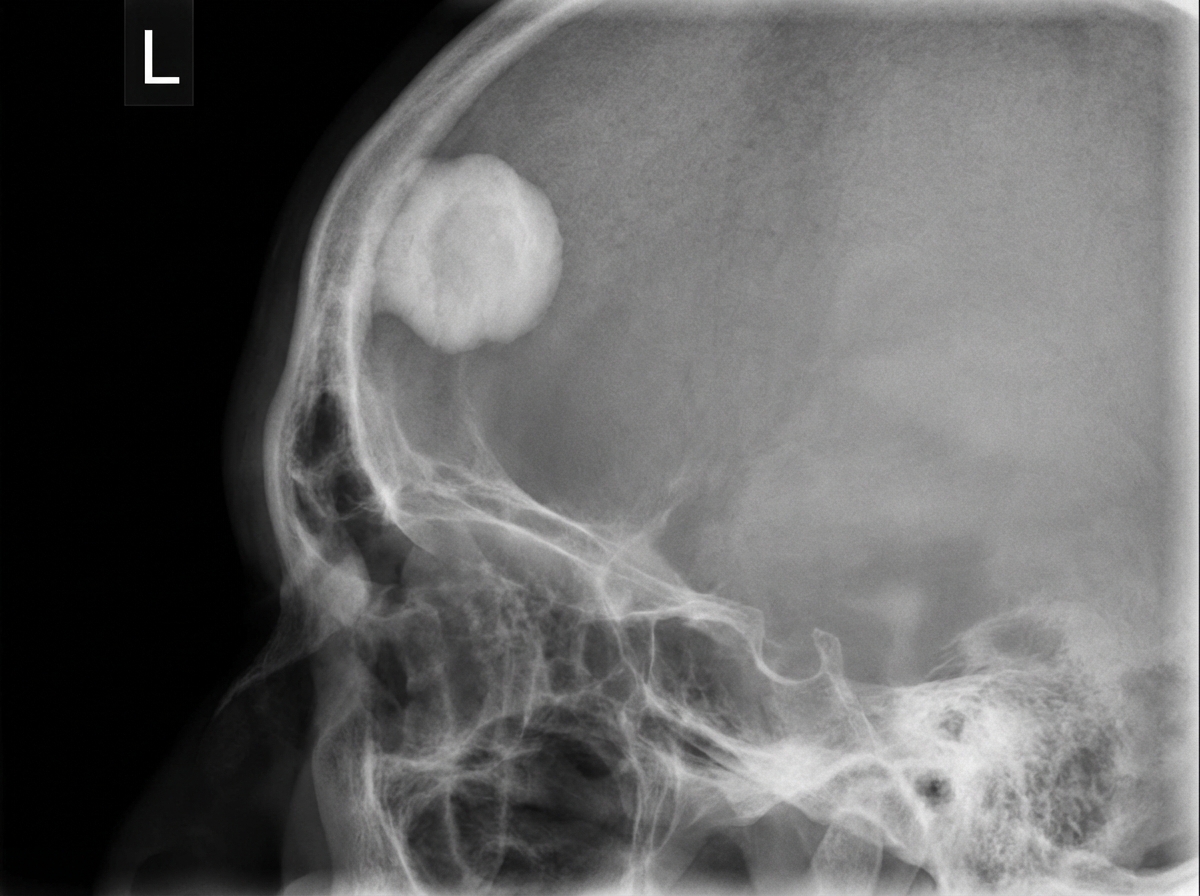

An X-ray film of the skull is provided. What is the diagnosis?

Explanation: ***Osteoma*** - Classic skull X-ray appearance shows a **dense, well-circumscribed, homogeneous ivory-like bony protrusion**, typically on the **frontal bone** or **paranasal sinuses**. - **Benign bone tumor** with characteristic **sclerotic appearance** and **smooth, round contours** without soft tissue involvement. *Osteoblastoma* - Appears as a **mixed lytic-sclerotic lesion** with **irregular borders** and possible **expansion** of bone cortex. - Typically larger than **2 cm** and shows **heterogeneous density** rather than the homogeneous ivory appearance of osteoma. *Sinusitis* - X-ray shows **fluid levels** or **opacification** within the **paranasal sinuses**, not solid bony masses. - May demonstrate **mucosal thickening** and **air-fluid levels** but lacks the dense bony protrusion seen here. *Multiple myeloma* - Characteristic **punched-out lytic lesions** with **no sclerotic margins** throughout the skull ("raindrop skull"). - Shows **multiple round radiolucent areas** without the dense, ivory-like appearance of osteoma.